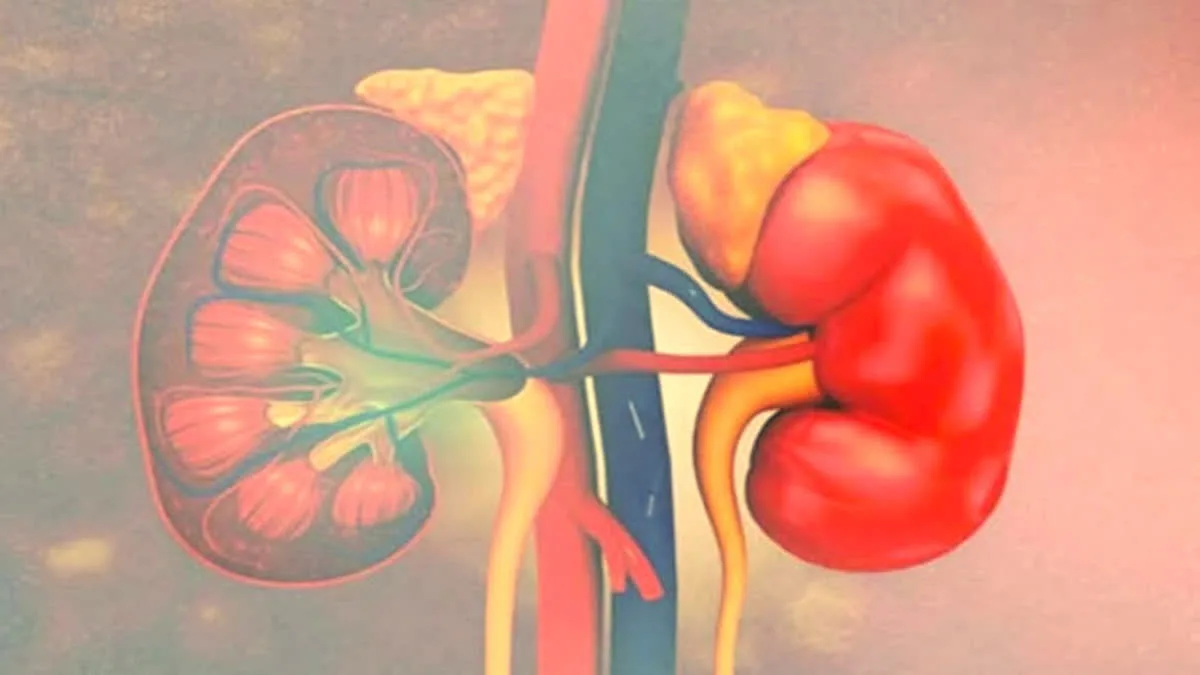

किडनी की बीमारी को “साइलेंट किलर” के नाम से जाना जाता है. यह अक्सर शुरुआती चरणों में बिना किसी स्पष्ट लक्षण के ही विकसित हो जाती है. आज के समय में, 8 से 10 प्रतिशत वयस्क किसी न किसी रूप में किडनी की क्षति से प्रभावित हैं. बहुत से लोग किडनी की बीमारी से तब तक अनजान रहते हैं, जब तक कि गंभीर जटिलताएं उत्पन्न नहीं हो जातीं. हर साल, लाखों लोग किडनी की बीमारी से जुड़ी जटिलताओं के कारण समय से पहले मौत के मुंह में समा जाते हैं. ऐसे मामलों में, शुरुआती लक्षणों की पहचान करने से काफी फर्क पड़ सकता है, खून और पेशाब की जांच जैसे साधारण टेस्ट, इस समस्या के गंभीर होने से पहले ही इसका पता लगाने में मदद कर सकते हैं.

‘विश्व किडनी दिवस’, जो हर साल मार्च के दूसरे गुरुवार को मनाया जाता है, का उद्देश्य किडनी के स्वास्थ्य की नियमित जांच की आवश्यकता के बारे में जागरूकता बढ़ाना है. 2026 का अभियान इस बीमारी का जल्दी पता लगाने पर केंद्रित है, और ज्यादा से ज्यादा लोगों से आग्रह करता है कि वे लक्षण दिखाई देने से पहले ही अपनी जांच करवा लें. बता दें, किडनी की बीमारी अक्सर बिना किसी लक्षण के ही बढ़ती रहती है, इसलिए, इसकी पूरी जांच (स्क्रीनिंग) ऐसी जटिलताओं को कम करने में अहम भूमिका निभाती है जिनसे बचाया जा सकता है. इस खबर में, हम ‘विश्व किडनी दिवस’ के महत्व पर चर्चा करेंगे और जानेंगे कि किडनी की बीमारी से बचाव के लिए नियमित जांच किसे करवानी चाहिए…

किडनी की बीमारी अक्सर बिना किसी खास लक्षण के ही शुरू हो जाती है, इसलिए जिन लोगों को इसका ज्यादा खतरा है, उनके लिए नियमित जांच करवाना बहुत जरूरी है. जांच करवाना खास तौर पर इन लोगों के लिए जरूरी है…